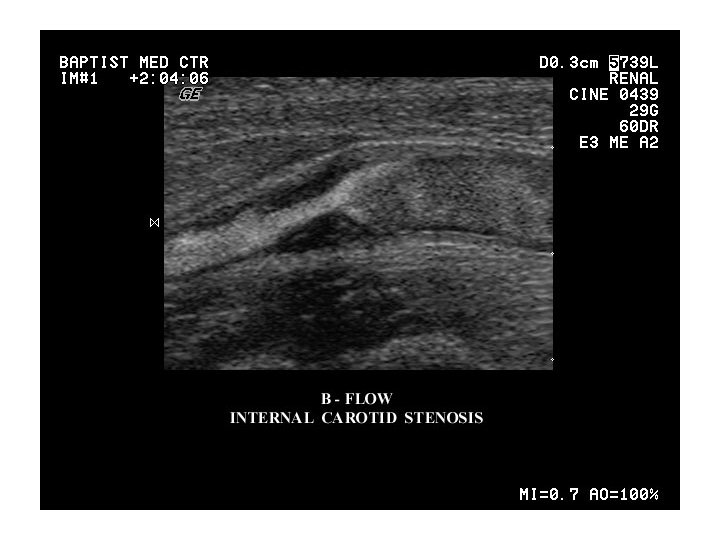

A. carotis interna – pars cervicalis • no branches in neck • lateral dorsal a. pharyngea dorsomedial to ACExt. ascendens • vagina carotica • sinus caroticus (baroreceptor) • trigonum caroticum + spatium parapharyngeum • spatium retrostyloideum • approach to ultrasound examination

Atherosclerosis(AL) Atherosclerosis • AT is clinically silent until critical stenosis / thrombosis / aneurysma/ emboly occurs • insufficient supply of peripheral tissue – intermitent claudication, angina pectoris – sudden closure: AIM, CMP diagnosis: angiography, ultrasound examination therapy: risk factors, LDL (statins)